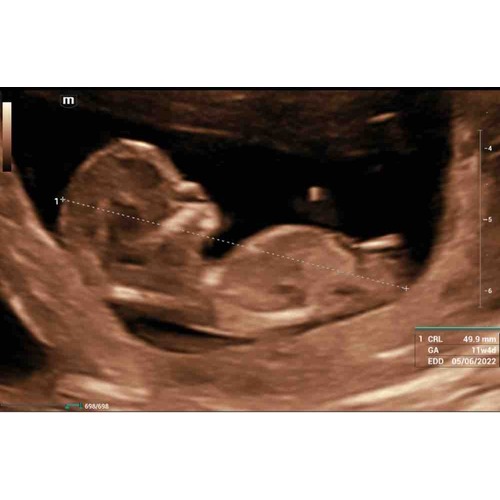

Wat denken jullie?馃グ馃挏 12wk6

Wat denken jullie 馃槉馃槉鉁ㄢ湪

Jongen

Jongen 馃槉